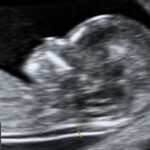

- Ecografía Transvaginal